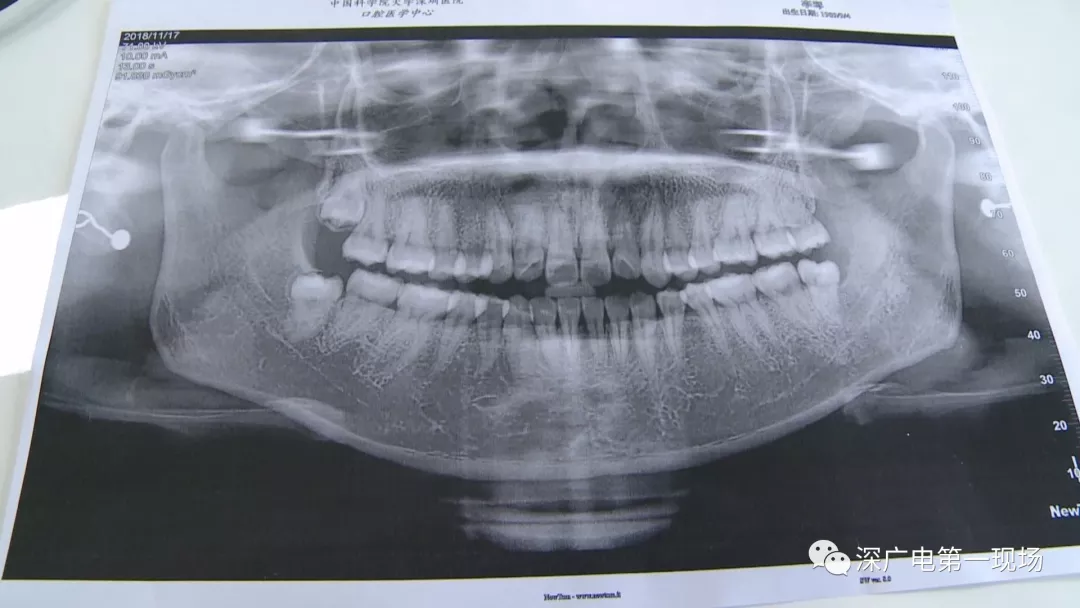

中國科學院大學深圳醫(yī)院口腔科主任賈岳介紹,對于不同患者的牙齒,它的治療方法都不一樣,所以不同牙齒,醫(yī)院收費的標準也各不相同。牙齒的治療方案,都是根據(jù)患者牙齒具體情況來制定,然后再去收費,同時也會參考病人實際情況來做不同的治療項目。